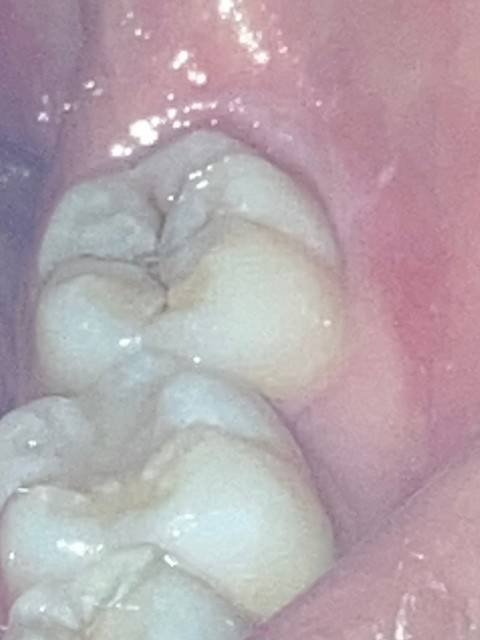

하 망했다 이거 충치맞지...ㅜ

아직 아프지는 않아

안아플때 가야 싸다

하 빨리 가야지...

지금 가면 싸

긁었을때 검은색 긁히면 진행! 안 긁혀나오면 정지우식! 치과가서 의사한테 물어방 빨리 가는게 통장을 지키는거야…

오우 나 저랬는데 30마넌 나옴

헐 진짜 다행이다... 난 10마넌에 레진으로 떼웠어!!

헉 내가 덤탱이 당한건가.....!!! 어쨌든 얼마 안나와서 다행이여....

당장 가.. 나는 겉으로 봐서 티가 진짜 안나서 긴가민가하면서 미루고 미뤘는데 어느날 넘 아파서 가보니까 안이 엄청 썩어서 신경치료함..

나 10만원에 레진 했어ㅜ 진짜 여기서 끝난게 다행인듯...

착색일수도 있음.

나도 어금니랑 사랑니에 저렇게 있는데 착색임. 근데 혹시 모르니까 가서 엑스레이 찍어봐

저정도 충치도 치료 받아야됨? 나 저상태로 스케일링 받고 쌤이 전체 살펴봐주셨는데 아무문제 없다 그러던데